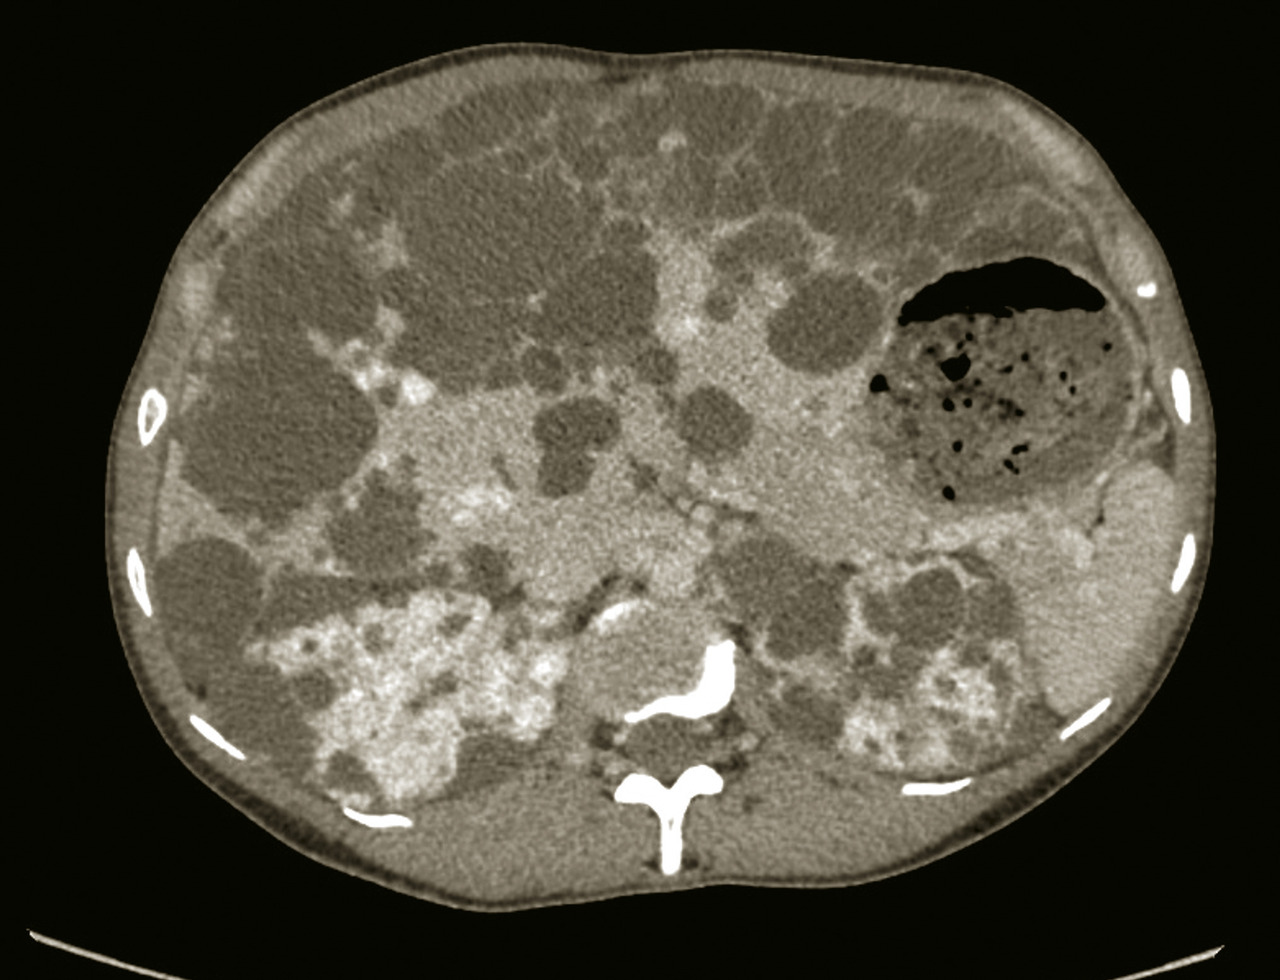

Une imagerie en coupe, tomodensitométrie (TDM) ou imagerie par résonance magnétique (IRM), avec étude triphasique (temps artériel, portal et tardif) après injection de produit de contraste, peut être utile au diagnostic étiologique d’une hépatomégalie.

◗ Donner les caractéristiques du carcinome hépatocellulaire en imagerie injectée : aspect hypervasculaire au temps artériel (phénomène de wash-in), et hypovasculaire au temps portal ou tardif (phénomène de wash-out) par rapport au parenchyme hépatique adjacent.